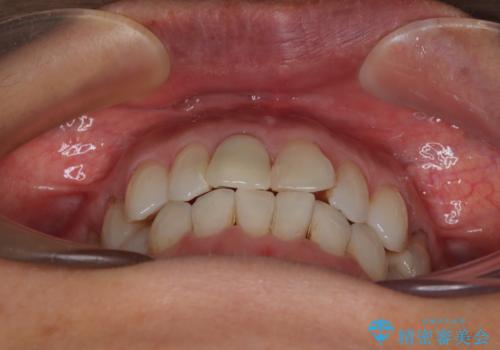

デコボコと銀歯 矯正治療とセラミック治療で綺麗な口元に

- 前歯のデコボコと口を開けたときに見える銀歯を気にして来院された患者様です。

矯正治療後に銀歯をセラミッククラウンなどに置き換えていくと、どうしても後戻りを起こしてしまうため、矯正治療が概ね終了した時点で銀歯を全てセラミックとし、最後に仕上げでインビザラインにを用いて細かいデコボコを改善していくこととしました。

とても明るい口元となり、人目を気にせず、大きく口を開けて笑えるようになりました。